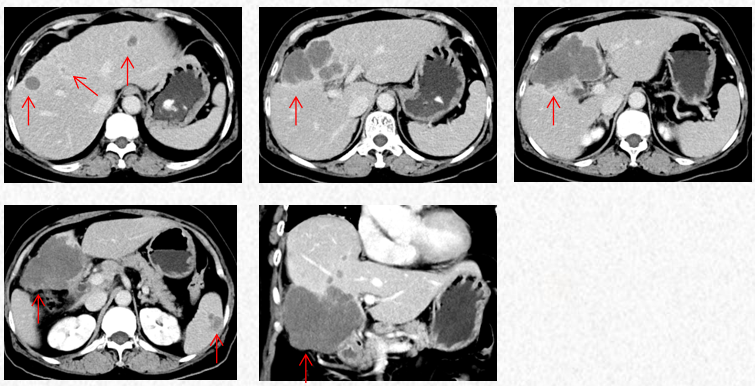

2022-10-9中南大学湘雅二院行PET/CT:肝左内叶和右前叶糖代谢增高肿块(最大横截面积10*8cm,SUVmax17.9),考虑恶性肿瘤(肝癌?胆囊癌累及肝脏?),累及胆囊及结肠肝曲及周围腹膜腔。肝门、门腔静脉间、右中腹(大网膜走行区)多发糖代谢增高的肿大淋巴结(大者约13*20mm,SUVmax 8.6),考虑淋巴结转移。盆腔子宫左后方糖代谢增高结节灶(最大横截面积15*14mm,SUVmax11.3),考虑转移所致(卵巢转移?腹膜转移)。

2022-10-9中南大学湘雅二院PET/CT

2022-11-30胸腹CT:肝肿物最大横截面积107*80mm(原病灶10*8cm),腹腔淋巴结最大10mm。新发脾脏转移瘤大小27*15mm。

2023-3-19胸腹CT:肝肿物最大横截面积91*60mm,脾脏转移瘤(19*12mm)

2023-5-22胸腹CT:肝肿物最大横截面积86*58mm,脾脏转移瘤(19*12mm)

2023-7-15胸腹CT:肝肿物最大横截面积86*58mm,脾脏转移瘤(19*12mm)